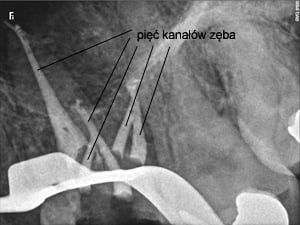

Pacjent lat 28 trafił do naszego gabinetu z powodu z powodu ćmiących dolegliwości bólowych zęba trzonowego górnego. Był on uprzednio leczony endodontycznie, lecz nie spowodowało to ustąpienia objawów. Po skierowaniu na leczenie endodontyczne przy użyciu mikroskopu zabiegowego uwidoczniono dodatkowy – czwarty i piąty kanał zęba. Po opracowaniu chemo – mechanicznym całego systemu korzeniowego i wypełnieniu kanałów termiczną gutaperką dolegliwości ustąpiły a ząb został odbudowany ze wzmocnieniem włóknem szklanym. Takie standardowe postępowanie lecznicze często obecnie wzbogacane o diagnostykę trójwymiarową 3D przy użyciu tomografii wolumetrycznej CBCT pozwala na jeszcze skuteczniejszą terapię endodontyczną i eliminację bólów często pierwotnie trudnych do zdiagnozowania i wyleczenia.